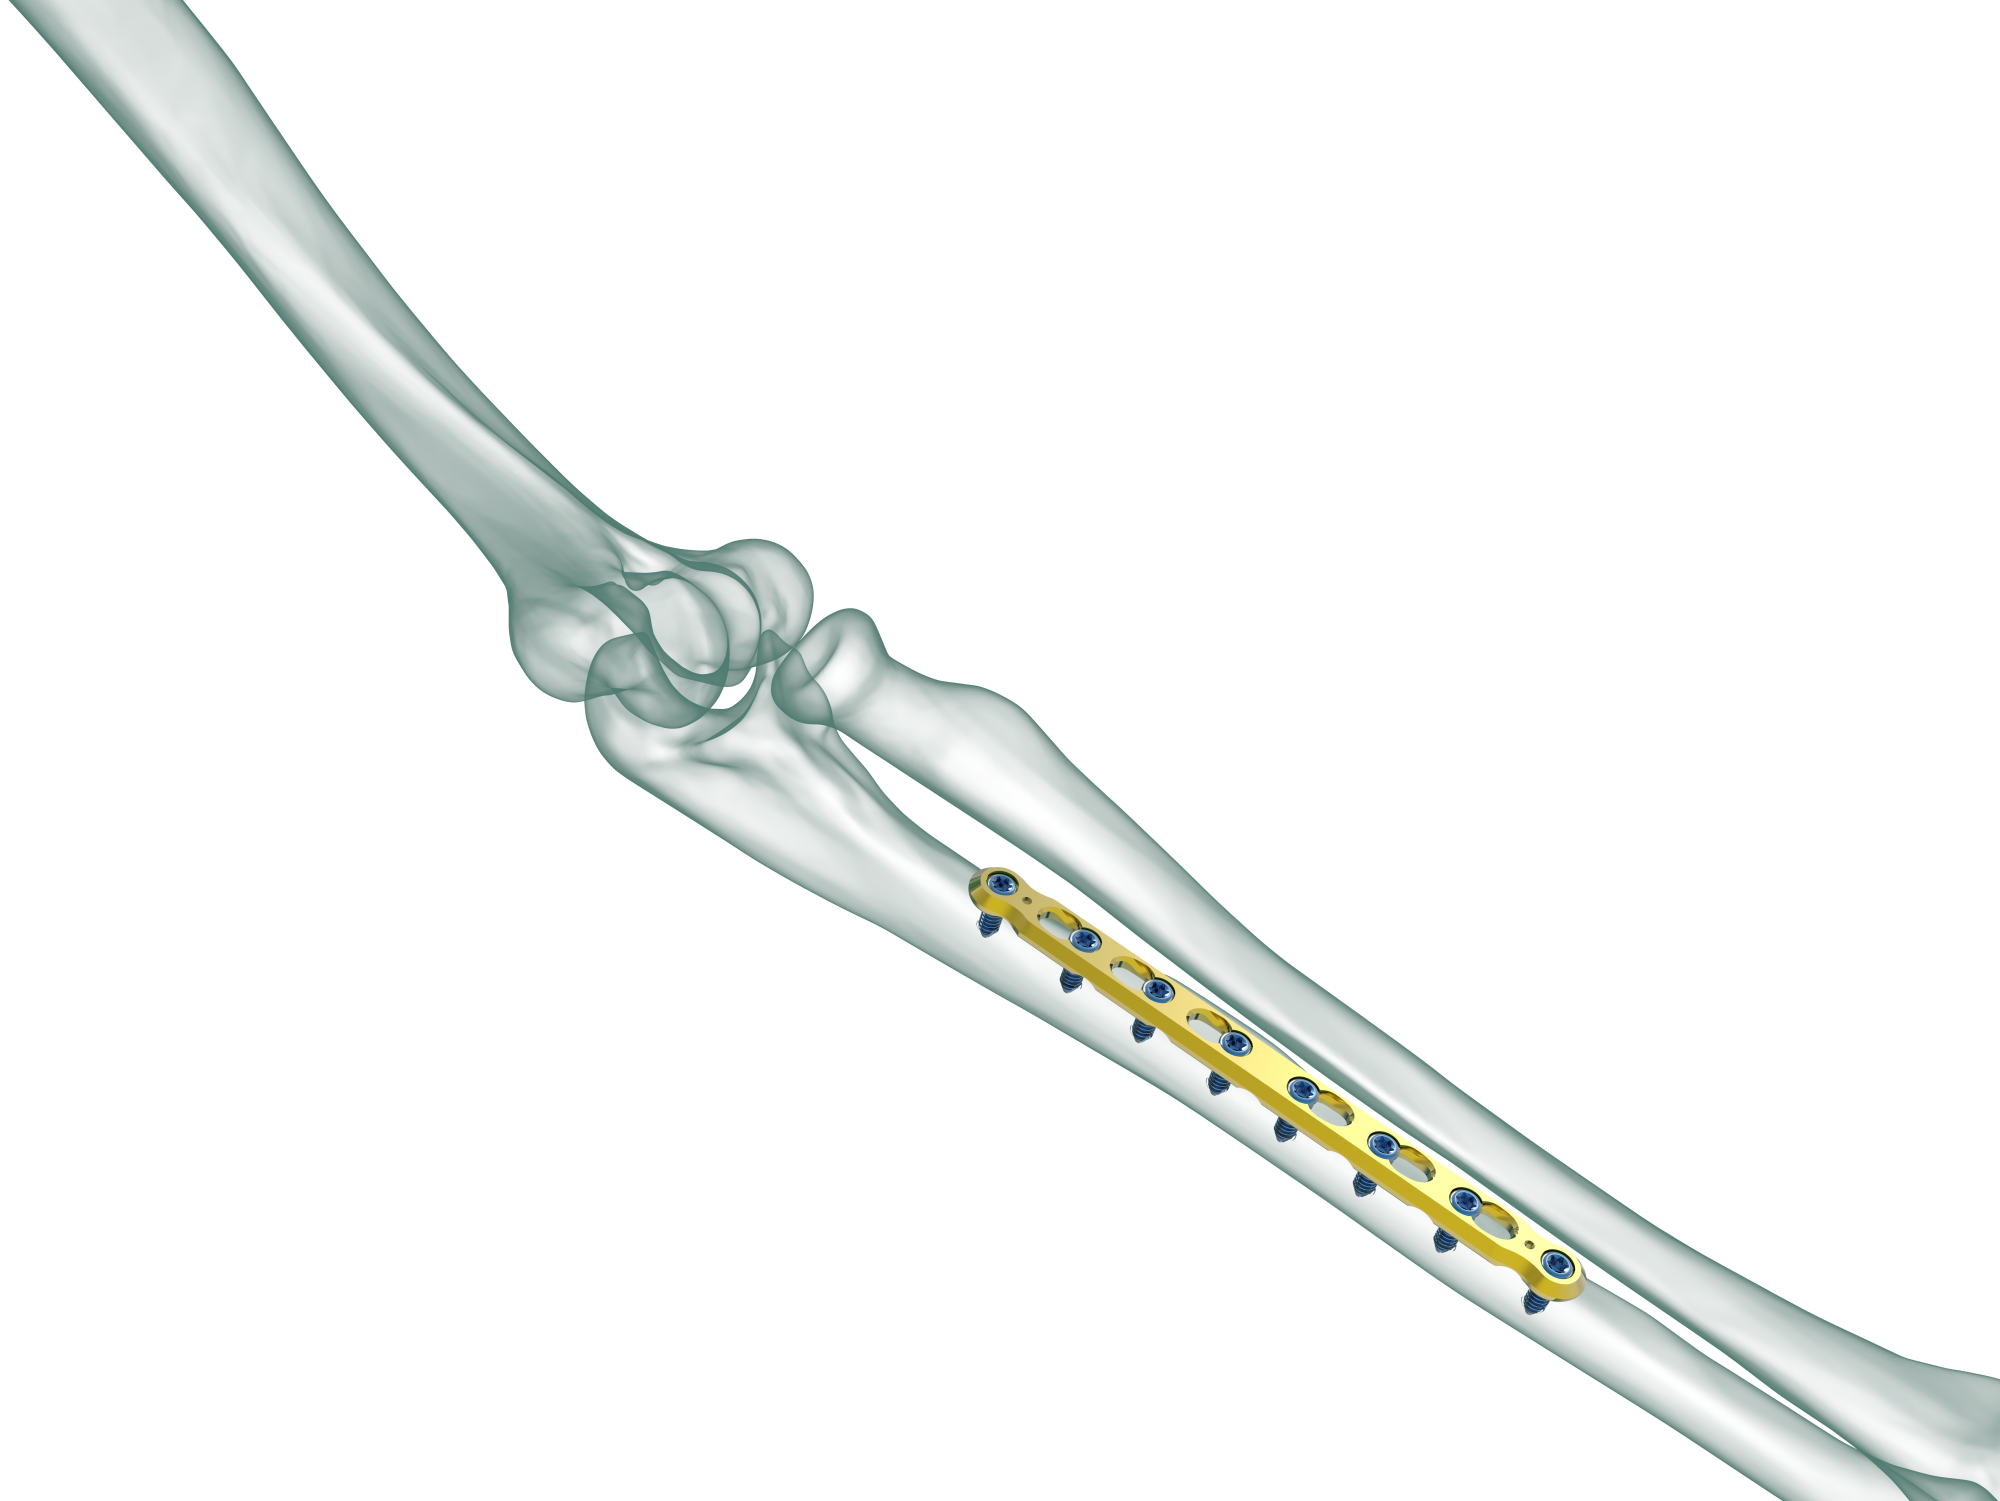

TRUE LOCK 3.5mm Ulna Radius Plate

TRUE LOCK 3.5mm Ulna Radius Plates are indicated for fractures of ulna, radius and fibula shaft.

Radius and ulna body fractures differ from other diaphyseal fractures due to the relationship between both bones and the fractures can affect the elbow and wrist joints. In adulthood, forearm fractures often require surgical treatment, as they are noticeably displaced and unstable.